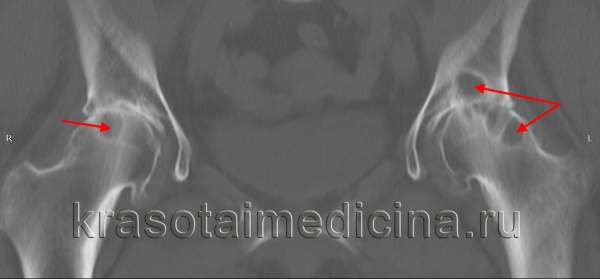

Важнейшим исследованием, имеющим решающее значение при постановке диагноза болезнь Пертеса, является рентгенография тазобедренного сустава. При подозрении на данное заболевание выполняются не только снимки в стандартных проекциях, но и рентгенограмма в проекции Лауэнштейна. Рентгенологическая картина зависит от стадии и выраженности болезни. Существуют различные рентгенологические классификации, наиболее популярными из которых являются классификации Кэттерола и Сальтера-Томсона.

- 1 группа. Рентгенологические признаки болезни Пертеса слабо выражены. Выявляется небольшой дефект в центральной или субхондральной зоне. Головка бедра имеет нормальную конфигурацию. Изменения в метафизе отсутствуют, линия перелома не определяется.

- 2 группа. Контуры головки не нарушены, на рентгенограмме видны деструктивные и склеротические изменения. Есть признаки фрагментации головки, определяется формирующийся секвестр.

- 3 группа. Головка поражена практически полностью, деформирована. Выявляется линия перелома.

- 4 группа. Головка поражена полностью. Выявляется линия перелома и изменения вертлужной впадины.

- 1 группа. Субхондральный перелом определяется только на рентгенограмме в проекции Лауэнштейна.

- 2 группа. Субхондральный перелом виден на всех снимках, наружная граница головки не изменена.

- 3 группа. Субхондральный перелом «захватывает» наружную часть эпифиза.

- 4 группа. Субхондральный перелом распространяется на весь эпифиз.